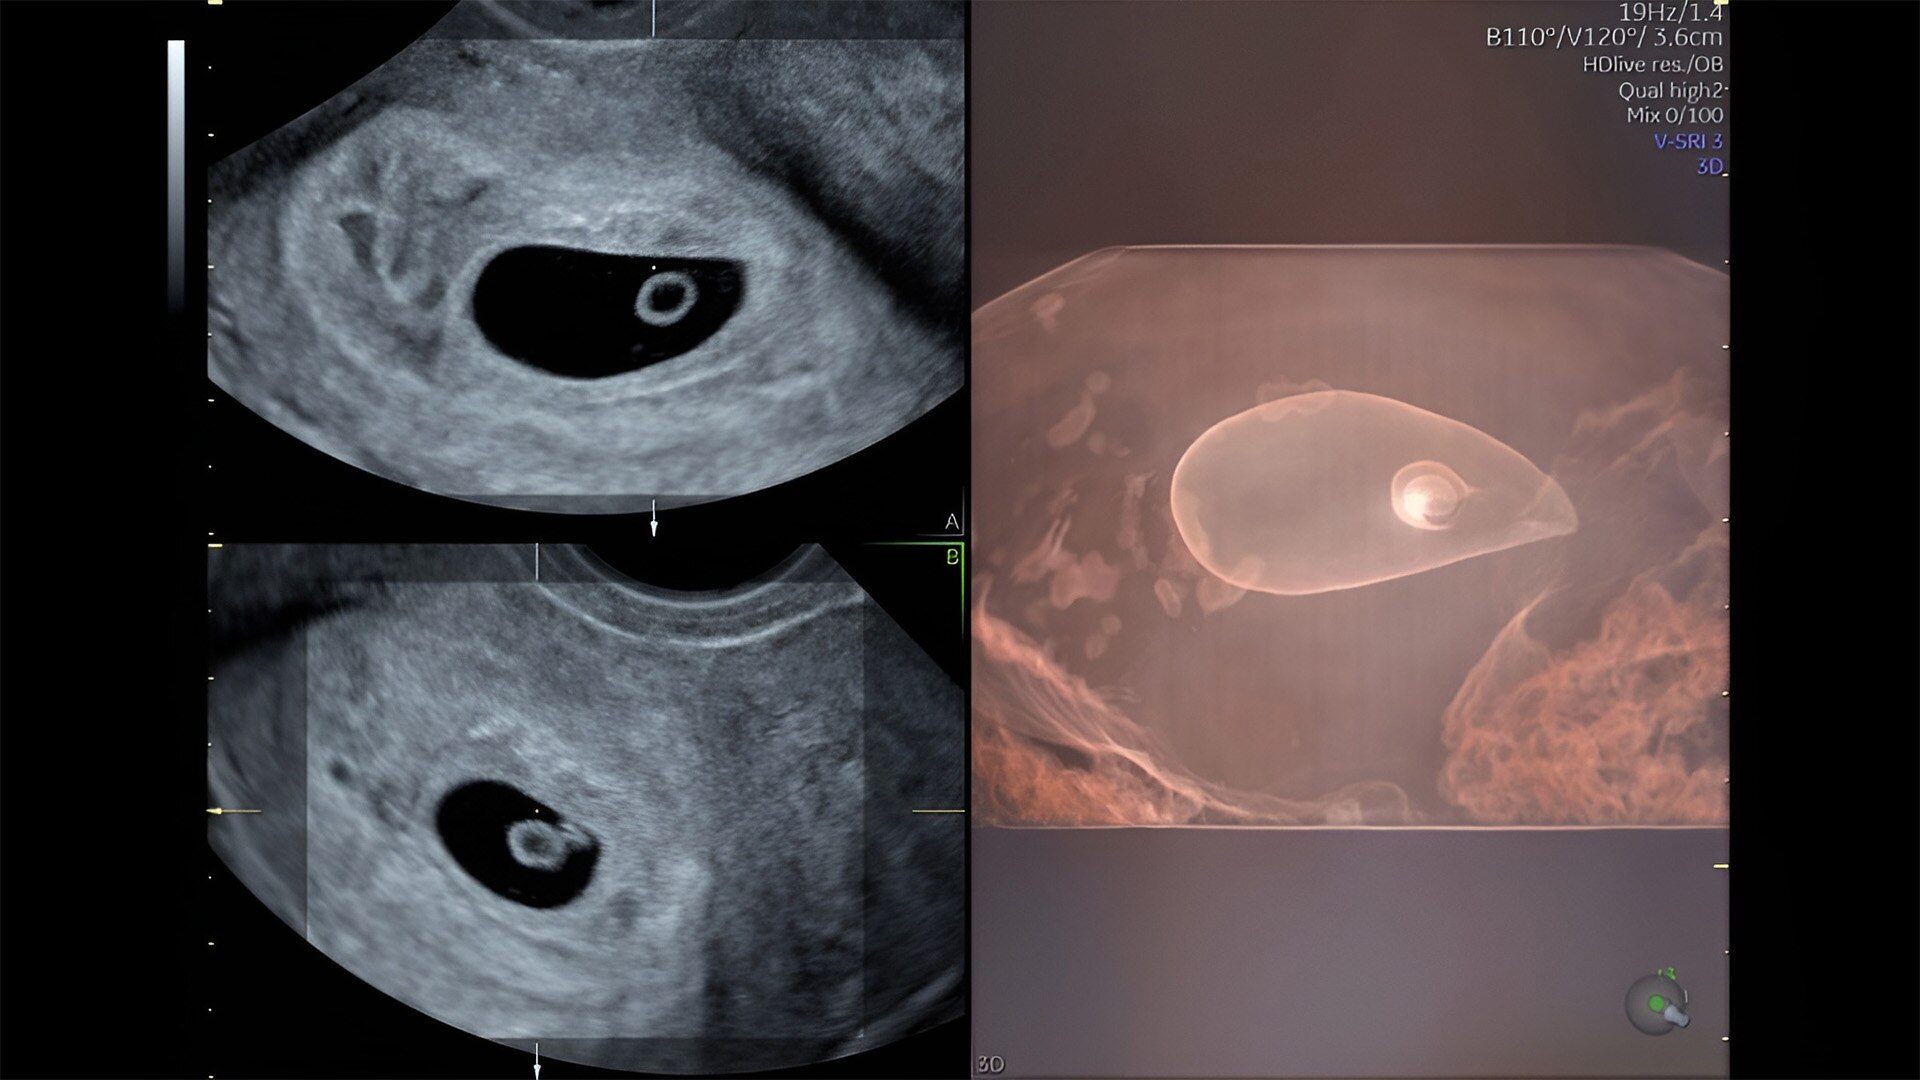

First trimester exams

Perform detailed exams with high-resolution for early insights to fetal health